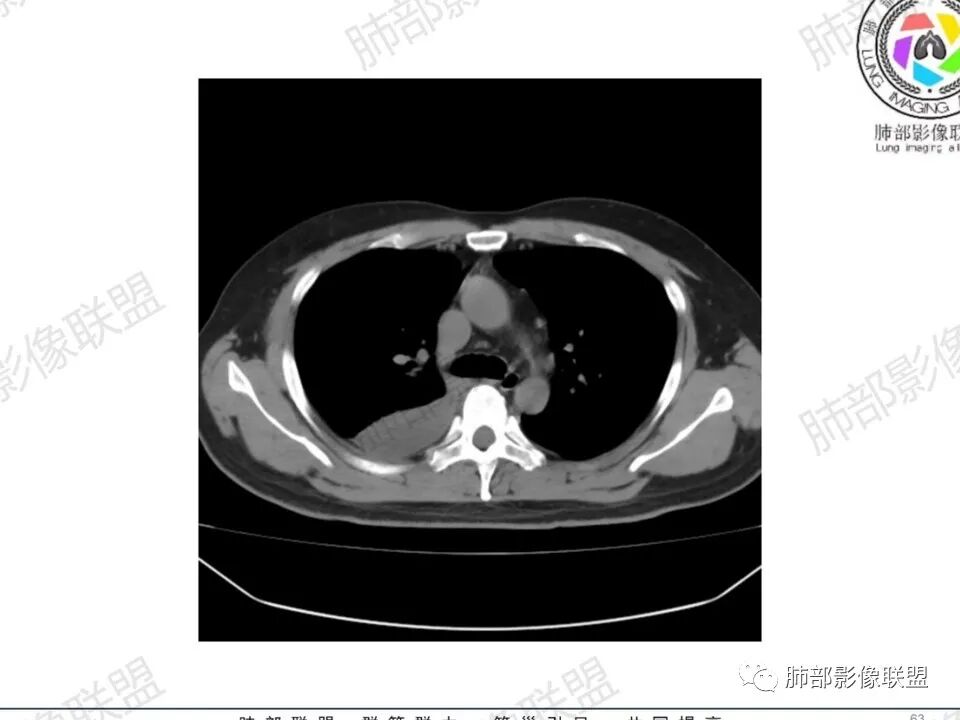

双肺多发结节,胸膜下为主,部分可见空洞。左肺上叶尖后段结节较大,分叶毛刺,周围可见长条索及小斑片影,内空洞比较光滑,内侧壁可见支气管通过。右肺下叶后基底段不张实变,后侧积液,右侧水平裂积液,右侧膈胸膜纵膈胸膜增厚积液,右侧侧胸膜肥厚,考虑1:一元金葡。2二元:金葡,左肺上叶结核。

男,45岁,左手指红肿疼痛两天,右侧胸壁疼痛伴发热12小时入院。患者急性起病,胸部CT示双肺多发结节,部分伴空洞,空洞壁较光滑,右侧胸腔积液,考虑感染性病变,金葡菌加SPE可能

中年男性,左手中指及胸壁疼痛伴发热来诊,影像见双肺多发结节,胸膜下分布为主,部分结节可见空洞,边缘模糊。左肺上叶尖后段结节较大。右肺下叶后基底段不张实变,右侧叶间裂及右侧胸腔积液,右侧侧胸膜肥厚。考虑金葡菌感染,血播SPE。

两肺多发结节空洞,随机分布,右肺下叶部分病灶实变并胸膜腔少量积液,有皮肤破溃,手指疼痛,发热,考虑感染性变,金葡可能性大。

有胸腔积液更提示血道来源